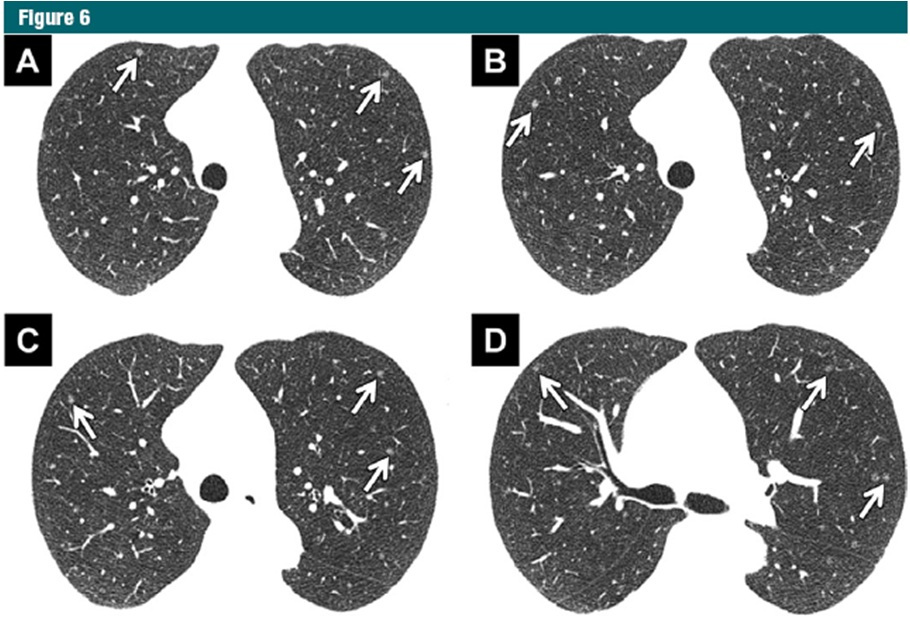

多發(fā)的肺部結(jié)節(jié)確實(shí)越來越多。許多患者很焦慮,對醫(yī)生的臨床決策也是一種考驗(yàn),需要把握好尺度是否為手術(shù)適應(yīng)癥,考慮到患者耐受和肺功能損傷,做手術(shù)能否一起切掉,比如一個(gè)肺葉內(nèi)三個(gè)結(jié)節(jié),切一個(gè)肺葉就能解決;但更多的是左、右肺都有,在切不干凈的情況下,需要確定哪個(gè)是主病灶,可能會(huì)帶來轉(zhuǎn)移等危害,要把最嚴(yán)重的、最危險(xiǎn)的優(yōu)先解決掉。如果病人有許多結(jié)節(jié),且在現(xiàn)階段醫(yī)療水平切不干凈,無法解決根本問題的情況下,等主病灶發(fā)展變化時(shí)再動(dòng)它。并不是所有的病灶都是要外科處理,還可以可以考慮放療等方式。